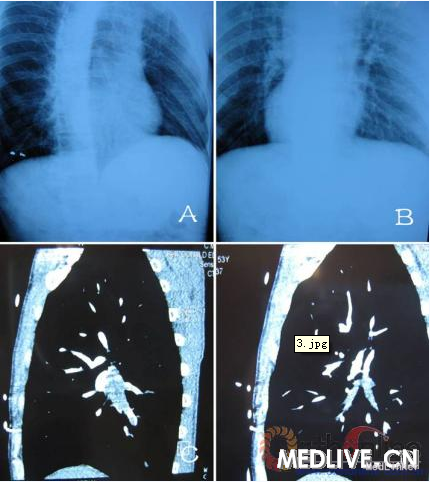

患者田某某,男,53岁,汉族,以“摔伤后左髂部疼痛肿胀3小时”为主诉入我院骨科住院治疗,经骨盆CT以及骨盆3D重建显示左髂骨翼骨折(见图1),临床诊断为左髂骨翼骨折。入院后给予保守治疗,卧床、制动,预防肺内及尿路感染。由于经济原因未予以华法林、利伐沙班等抗凝药预防治疗,6天后出院。回当地医院继续治疗,用促进骨愈合以及活血化瘀的中药,治疗期间左下肢较右下肢略肿胀,但未见明显肿胀。伤后20天在进行功能康复锻炼时突然出现胸痛、胸闷、呼吸困难,同时伴左下肢轻微肿胀(见图2),转入我院急诊抢救治疗。血气分析:PC02:33mmHg,P02:82.8mmHg;D-二聚体:20µg/ml;生化指标:AST:44U/L,LDH:257U/L,CK-MB:2.0u/L,TNI<O.5 µg/L;心电图:未见异常。肺动脉增强CT显示右肺中间动脉内见低密度影,造影剂充盈缺损,右肺中叶、双肺下叶及分支内均可见低密度影,部分分支内见少许造影剂显影。影像学诊断为双侧肺动脉多发栓塞,以双肺下叶动脉及右肺中叶动脉为著(见图3)。超声检查:左下肢股静脉内径约1.13cm,股浅静脉内径约0.63cm。股深静脉内径约0.7cm。腘静脉内径0.7cm,内见血栓样回声,未见明确彩色血流显示。超声诊断为左下肢深静脉血栓形成。给予低分子肝素钙(速碧林)0.4 ml每12小时皮下注射7天,吸氧,制动,同时华法林2.5 mg每日1次口服抗凝治疗,渐增量至3mg每日1次,定期检测监测凝血三项,国际标准化比值(INR)维持在2.5~3.0。由于患者经济原因,未行溶栓治疗、血栓抽吸及滤器的安装。治疗一周后患者胸痛、胸闷、呼吸困难等症状明显减轻,1个月后胸片示右下肺动脉及心影大小正常。